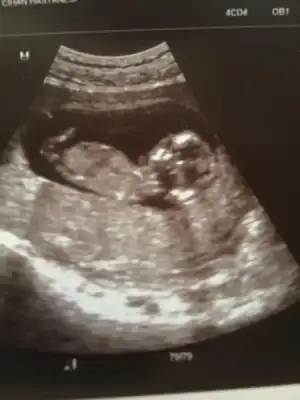

selam kızlar. Bugün kontrolümüz vardı minnağım kocaman olmuş el ayak sallar hale gelmiş :) 10+1 dik ama 2 gün önde gidiyor benimki 1 aydır o yüzden 10+3 ölçüyor usg. Fotoda nub gözükecek şekilde çıkmamış ama ben yinede bir şansımı deniyim kızlardan bir tahmin almaya çalışıyım dedim. Doktorum cinsiyet tahmini için 1,5 ay sonra dedi kim beklicek okadr çatlarım ben :) Bakın bakalım bişiler görebilecekmisiniz canlarım :16:

• $10+1 - 10+3 (2) - Kopya.webp

$10+1 - 10+3 (2) - Kopya.webp

20,8 KB · Görüntüleme: 104